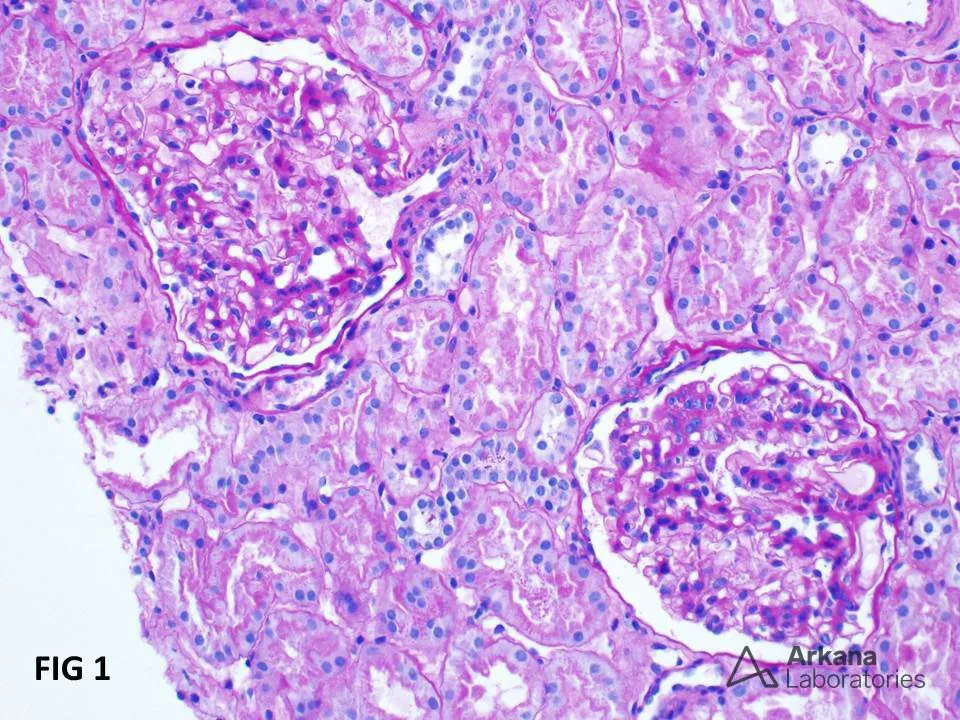

a NIgA, esperar proteinúria “alta demais” é perder tempo. A KDIGO 2025 destaca: ≥ 0,5 g/d já indica risco e exige ação precoce — biópsia, metas claras e plano terapêutico integrado para mudar a história da doença.